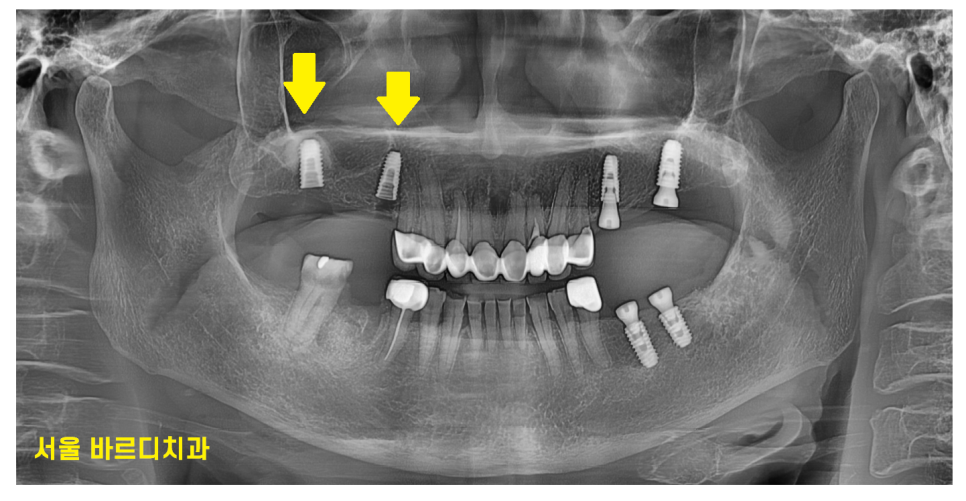

230728

목이 부러져서 건들거리는 왼쪽 아래가

제일 불편하다고 하셔서

위 아래 임플란트를 왼쪽부터 1차 진행

한달 뒤 오른쪽 임플란트 수술을 진행했습니다.

230829

오른쪽 수술을 마친 직후입니다.